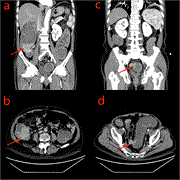

Simultaneous bilateral deep femoral artery aneurysms: case report of a rare peripheral arterial aneurysm

Rahel Abebayehu Assefa and others

Journal of Surgical Case Reports, Volume 2025, Issue 1, January 2025, rjae821, https://doi.org/10.1093/jscr/rjae821